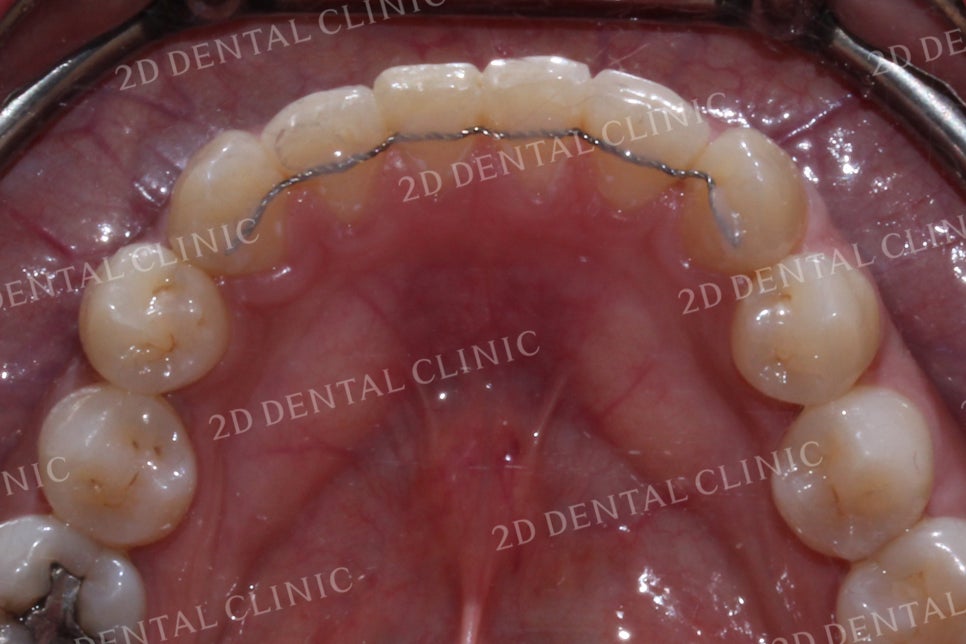

반대교합 교정 후

반대교합으로 물리는 치아를 바른 교합으로 교정하기! by.투디치과(2D치과)

<Before> <After>

상악의 설측면에서 명확하게 느껴졌던

측절치의 경사가 교정 후 정상 경사로

바뀐 모습입니다.

반대교합 역시 치열이

가지런하게 바뀌면서

올바른 교합 상태로 바뀌었네요!